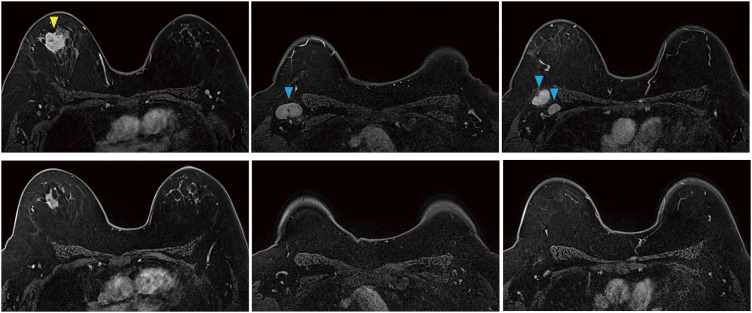

Case presentation: A 51-year-old woman was diagnosed with Stage II B TNBC and underwent NAC using pembrolizumab + paclitaxel + carboplatin. Her blood test on cycle 4, day 15 (C4D15) showed a significant decrease in platelets to <2000/μL accompanied by overt bleeding tendency. She was hospitalized for further investigation and treatment. Her platelet count recovered after platelet concentrate transfusion and corticosteroid administration. Her bone marrow examination showed normal cellularity, and she was judged as ITP. Due to the event and good clinical response to NAC, she underwent a right partial mastectomy and axillary lymph node dissection without completion of the planned NAC. The surgical specimen showed a complete pathological response.